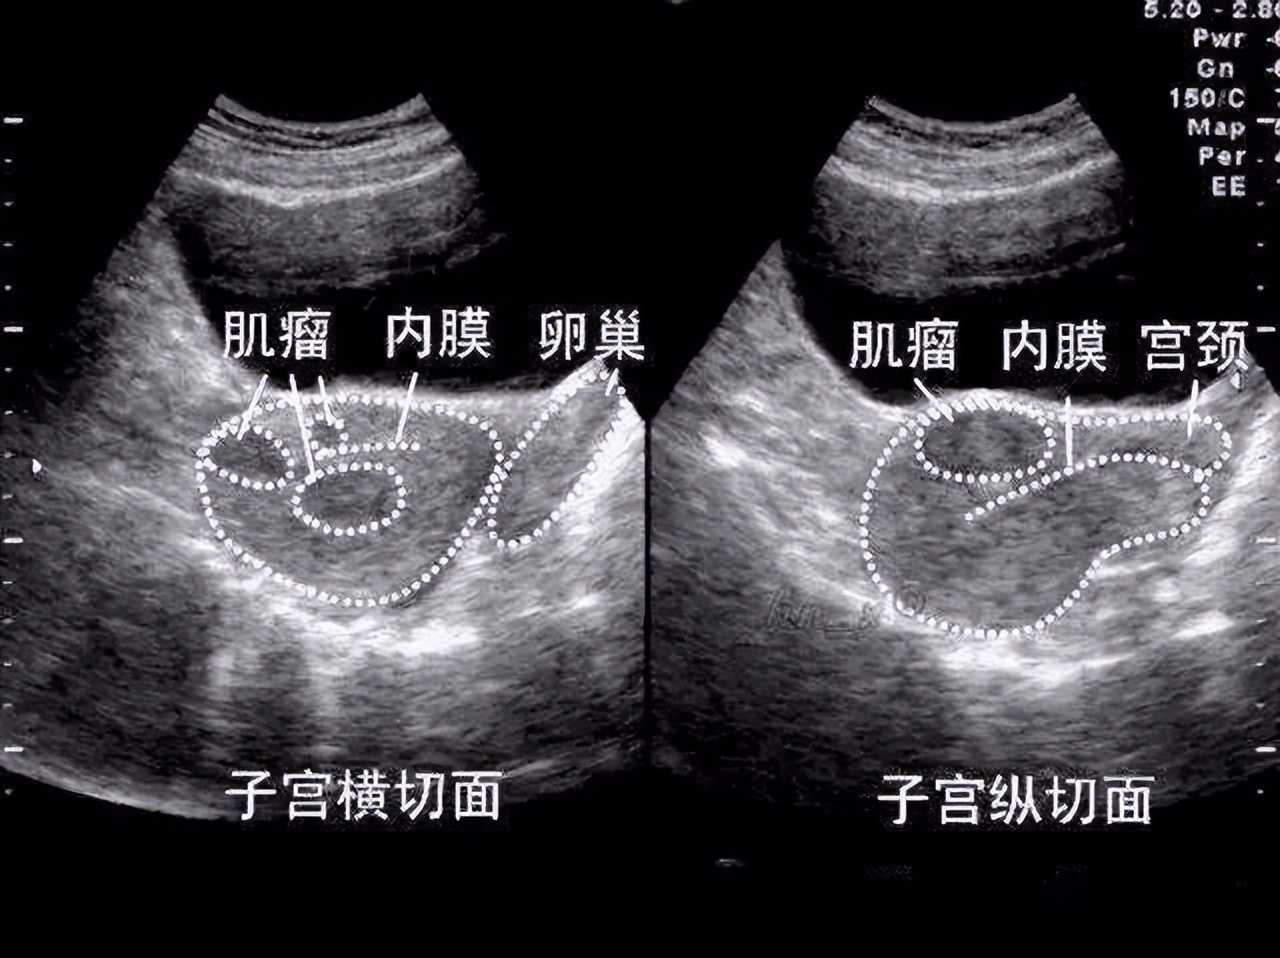

我们把子宫理解成一个房子,在房子里面长得肌瘤呢,我们叫粘膜下肌瘤,房子外面的肌瘤呢,叫浆膜下肌瘤,而在墙壁上的肌瘤呢叫肌壁间肌瘤。

越是往房子里面长得肌瘤,对怀孕的影响是越大的。

如果是粘膜下肌瘤,哪怕是1cm,在怀孕之前,也是建议要调理好再备孕,不然很容易出现流产和胎停的情况。

肌壁间肌瘤,如果比较大的并且是往房子里面长的,对怀孕可能会产生一些不利影响。

而房子外面的肌瘤,如果没有不舒服,可以尝试带瘤怀孕。